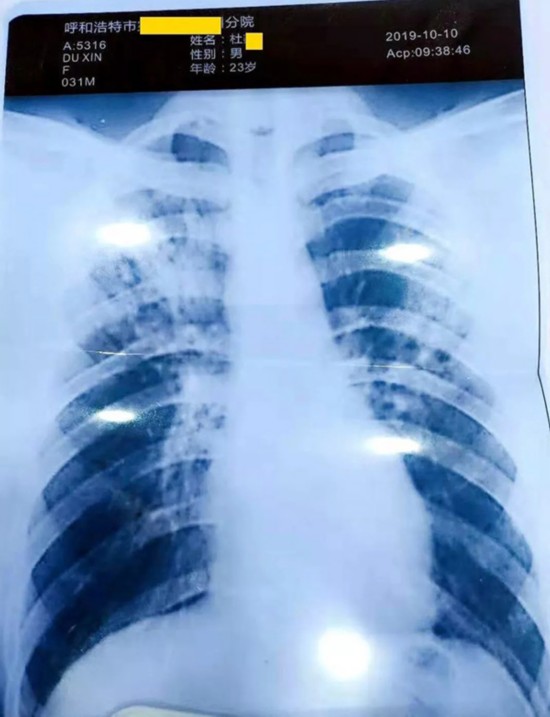

杜某找人伪造的胸片显示他得了严重的肺结核

当日下午,为了验证杜某的说法,由家长指定医院和医生,大家带着杜某去拍了胸片,并做了痰化验。诊断意见为,胸部平片未见异常。胸片也与杜某之前提供的胸片完全不同。

杜某的真实检查结果显示他并没有患上肺结核